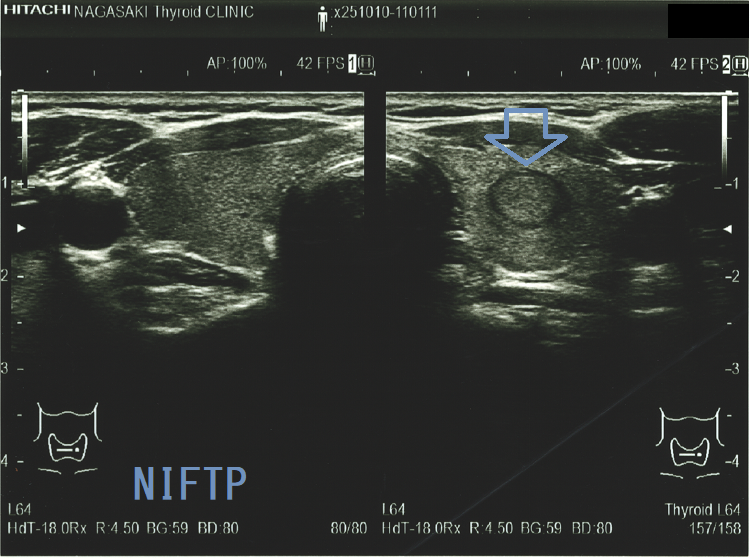

(a)Non-invasive follicular thyroid neoplasm with papillary-like nuclear features (NIFTP) 超音波(エコー)画像;見かけは濾胞型甲状腺乳頭癌、甲状腺濾胞癌、腺腫様結節と鑑別できまない

Non-invasive follicular thyroid neoplasm with papillary-like nuclear features (NIFTP)の超音波(エコー)所見は、

- 被膜が存在(被膜のない場合もある)

- 充実性、等エコーが多い

- 砂粒状石灰化を認めない

で、濾胞型甲状腺乳頭癌、濾胞性腫瘍(良性濾胞腺腫 、甲状腺濾胞癌)と超音波(エコー)所見にて鑑別できません。砂粒状石灰化のない濾胞型甲状腺乳頭癌なんて普通に存在します。NIFTPの60.1%は悪性を疑う所見が無いとされます[Endocrine. 2021 Jul;73(1):131-140.]。